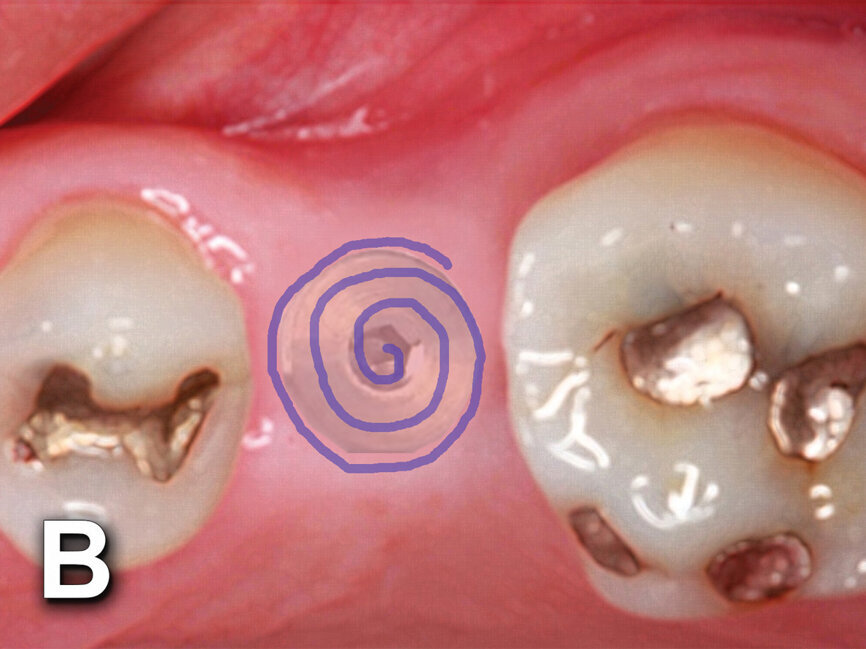

Fig. 4b: Implant to be uncovered (4a) presents with two options depending on width of attached gingiva available. Wide band of attached gingiva will remain after removal of tissue over cover screw, and the diode is utilized in a spiral pattern starting at center until fully exposed (4b). With the narrow band of attached gingiva present, an elliptical cut is made with the diode and tissue is pushed buccally and lingually to preserve the attached gingiva (4c). (Photo provided by Dr. Gregori M. Kurtzman)

The width of attached gingiva remaining will dictate the best method for implant uncovery (Fig. 4a). When a wide band of attached gingiva is present and a sufficient amount (3 mm or greater) will be present after uncovery on both the buccal and lingual, then the diode laser is activated and inserted at the center of the site and worked in a spiral pattern outward until the entire cover screw is exposed (Fig. 4b).